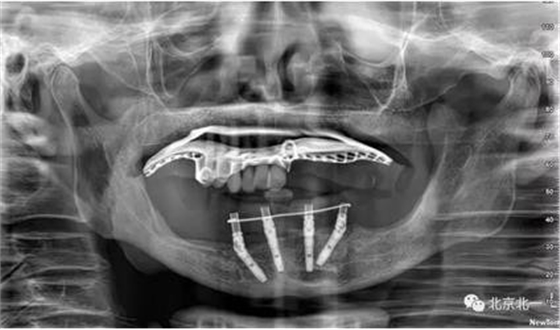

術(shù)前檢查片下頜骨季度萎縮,右側(cè)下頜下牙槽神經(jīng)管幾乎位于牙槽嵴頂。不能行常規(guī)種植。采用A04技術(shù)可實(shí)現(xiàn)即即刻種植一日戴牙夢(mèng)想。

圖一至圖六明顯看出右側(cè)頦孔位于牙槽嵴頂。很清晰看出頦孔區(qū)的U型形狀。

圖七:采用A04技術(shù),拔除下頜余留牙,修整骨平面。在頦孔前方傾斜植入兩枚植體,避開(kāi)頦孔。減少懸臂。前牙區(qū)植入兩枚直的植體。完成即刻修復(fù)。一日得牙,缺牙后多少年來(lái)都沒(méi)有吃過(guò)蘋果的滋味,到種植牙時(shí)代,想吃什么就吃什么, 我的健康我做主。